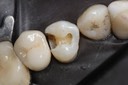

Kyle Chock #14 castings

Kyle Chock #14 castings on model